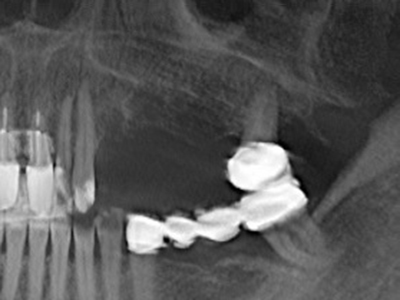

Fig. 17a: CT image of a growth-promoting osteotomy immediately adjacent to ...

Abb. 17b: the alveolar duct with nerve irritation (lateral and coronal view).